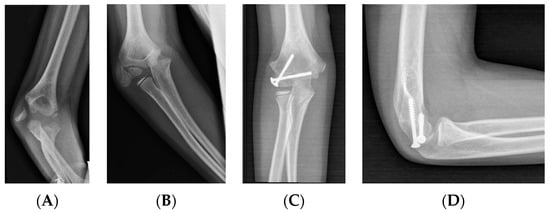

3.2.2. Open Reduction

3.2.3. Choosing the Reduction Method

3.2.5. Fixation: Cannulated Screws

3.2.6. Choosing the Fixation Strategy